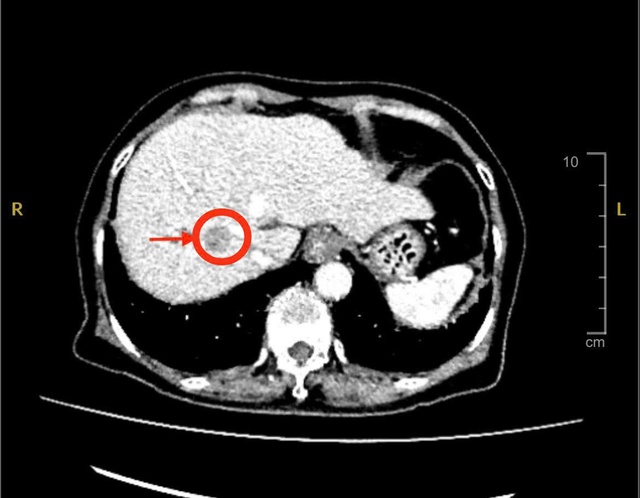

Ngày 9.11, thạc sĩ - bác sĩ chuyên khoa 2 Phan Văn Sơn, Khoa Ngoại tiêu hóa gan mật tụy, Bệnh viện đa khoa Xuyên Á cho biết, bệnh nhân được chỉ định siêu âm bụng và chụp MSCT thì phát hiện có khối u gan bên phải với kích thước khoảng 2 cm, nghĩ nhiều đến ung thư nguyên phát tế bào gan - một dạng ung thư gan phổ biến ở người có bệnh nền xơ gan, viêm gan B hoặc viêm gan C.

Hình ảnh CT khối u gan

Trong quá trình mổ, ê kíp đã thám sát và phát hiện khối u có kích thước chỉ khoảng 2 cm. Tuy nhiên, khối u không nằm trên bề mặt mà nằm sâu trong nhu mô gan, ở vị trí rất sát mạch máu lớn ở gan. Vì thế, các bác sĩ phải sử dụng siêu âm trong mổ để xác định chính xác vị trí khối u và khống chế tất cả các mạch máu lớn nuôi gan, tránh chảy máu ồ ạt.